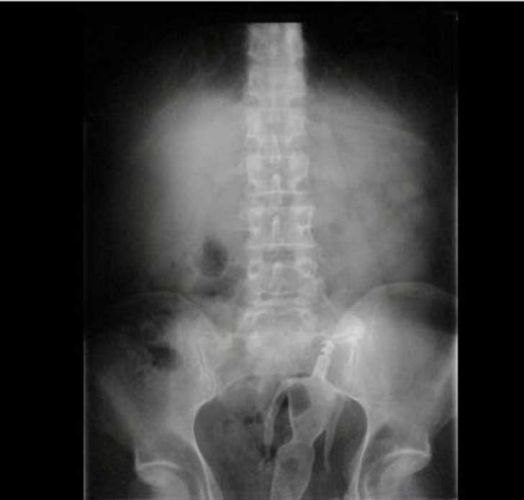

Os objetos mais BIZARROS encontrados no ânus pelos médicos